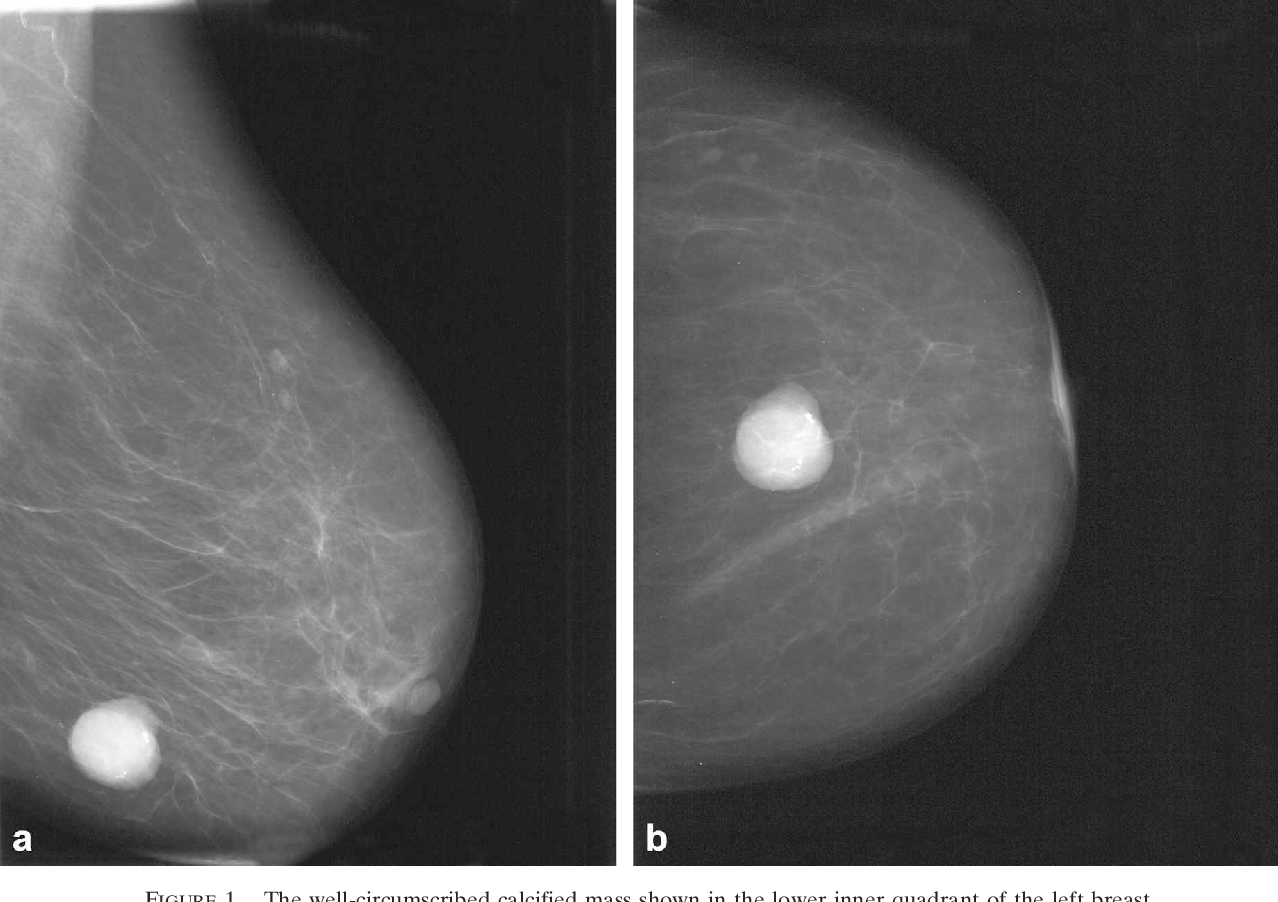

Фото раковой шишки на теле

Раковые шишки могут возникать не только на лице, но и на других частях тела. На фотографиях вы можете увидеть примеры раковых шишек на шее, руках, ногах и туловище. Обратите внимание на различные формы и размеры раковых шишек, а также на их внешний вид.